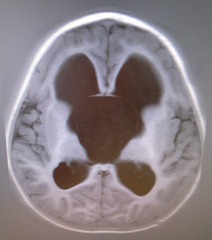

You can see that the new scan is much better than the old one.

You should be able to see that his brains are a lot less squished now which means that, although it is difficult to see, there are a lot more ridges.

Figure: This time we have the full scans

Because we are heading to the USA we will be needing the full history and Scans to take with us. So I have better pictures